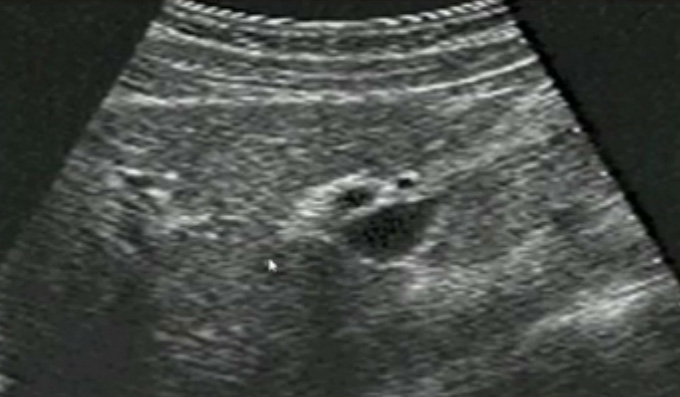

一、正常膽囊超聲圖像

膽囊的位置、形態(tài)、大小、壁厚,內(nèi)部及附壁是否有異?;芈?尤其膽囊要注意頸部,還要看有沒慢性炎癥的征象,腫瘤或隆起樣病變.正常膽囊聲像圖是像個瓣,膽囊正常大小,頸部指向肝門膽囊輪廓清晰,壁薄很光滑呈線狀,囊內(nèi)無回聲,后壁回聲增強(qiáng)。為什么無回聲呢?因?yàn)槟懼且后w,水,血液這些都是無回聲的。膽囊頸和門靜脈或門脈右支根部之間有一線狀高回聲帶連結(jié),這是識別膽囊位置的重要標(biāo)志。膽囊長徑一般不超90mm;前后徑2030mm,不超過40m正常充盈膽囊壁厚<3mm。 膽囊皺褶非常常見,